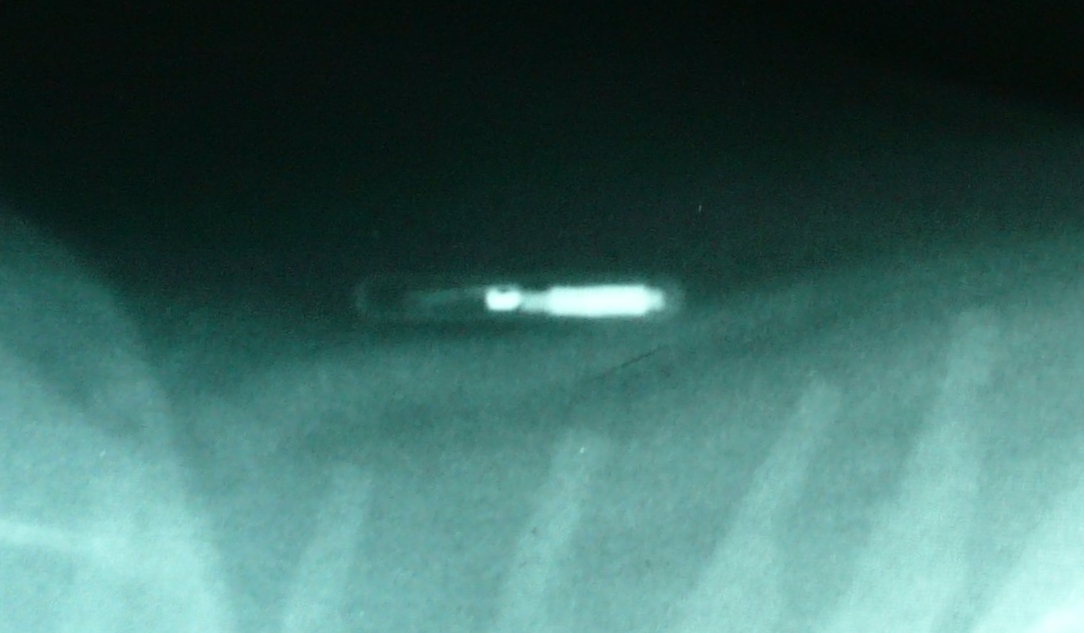

Transponderchip im Röntgenbild einer Katze

Foto: Hundehalter